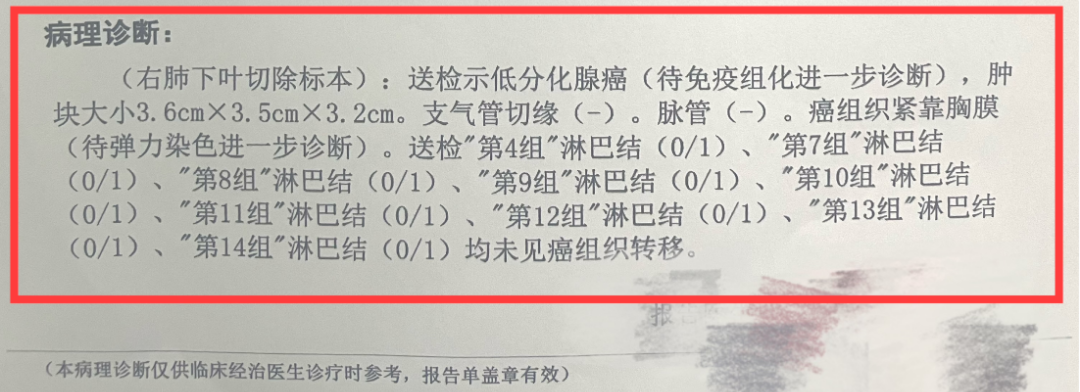

想知道肺手术中最重要的报告都告诉你什么了么?...

想知道肺手术中最重要的报告都告诉你什么了么?...